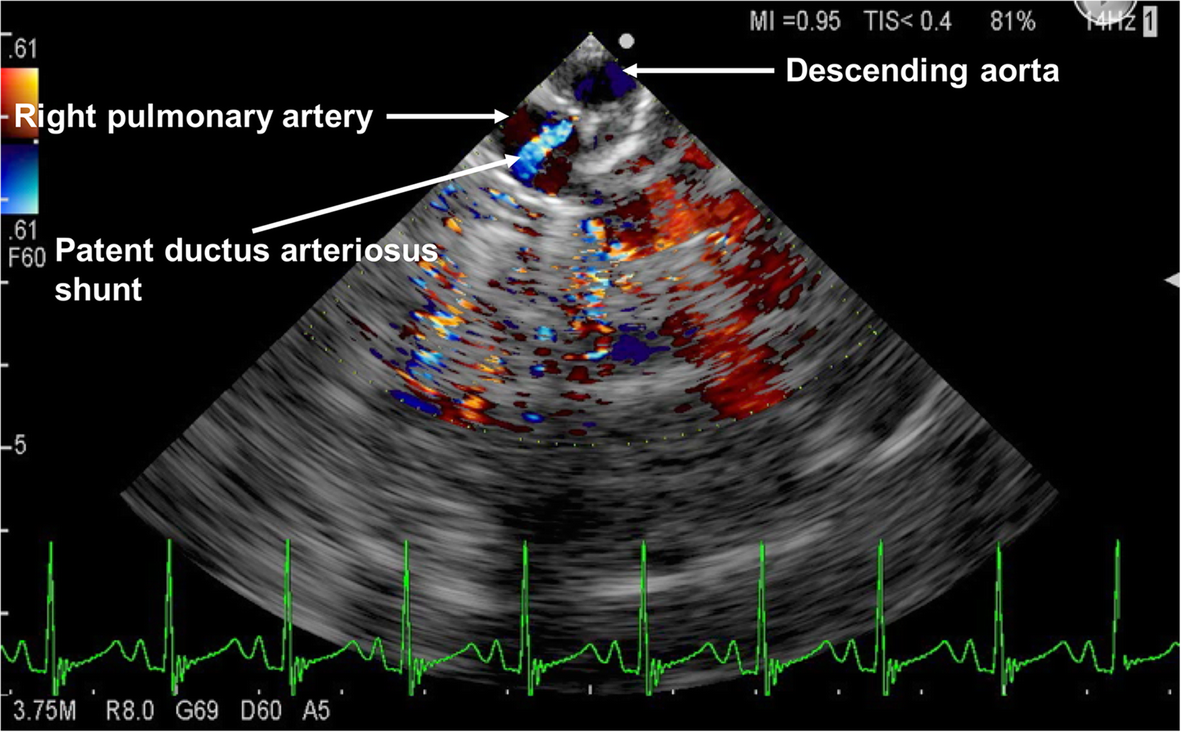

Echocardiography of the patent ductus arteriosus in premature infant

Patent Ductus Arteriosus and Aortopulmonary Window Echocardiography Pda Closure Echo The echocardiography is the investigation of choice to diagnose pda, estimating the magnitude of shunt volume and. This vessel typically closes shortly after birth, but can remain patent, particularly in premature infants, and is known as a patent ductus arteriosus (pda). This article reviews the echocardiographic signs of pda in preterm infants and the indications for closure. The patent ductus. Pda Closure Echo.